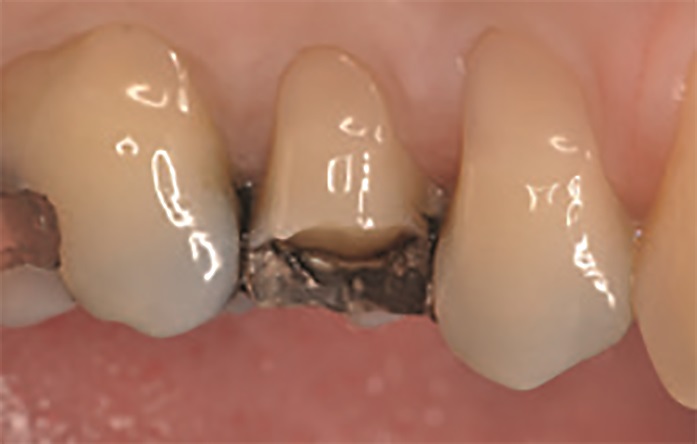

47‑letnia pacjentka zgłosiła się z powodu objawów zapalenia miazgi zęba 15. W badaniu wewnątrzustnym stwierdzono obecność starego wypełnienia amalgamatowego oraz złamanie guzka policzkowego zęba 15 (ryc. 1 i 2). W związku z tym na pierwszej wizycie przeprowadzono leczenie endodontyczne zęba 15 w znieczuleniu miejscowym (ryc. 3).